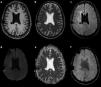

El paciente ha seguido controles mediante RM craneal, y en el estudio realizado en 2017 se detectó una lesión quística de nueva aparición en la corona radiata derecha, objetivándose un crecimiento progresivo en sucesivos controles (fig. 1). La exploración clínica del paciente no mostró ningún déficit o alteración neurológica de nueva aparición. Se trata de una lesión quística y septada, isointensa al LCR en todas las secuencias; sin gliosis ni edema circundante, sin restricción de la difusión ni realce tras la administración de contraste. Está situada en el campo de irradiación, y se encuentra rodeado de múltiples focos hemorrágicos puntiformes, visibles en secuencias de susceptibilidad magnética, en la sustancia blanca adyacente8 (fig. 2).

Estado de la lesión en RM de 2020. La imagen muestra secuencias T1-3D SPGR sin contraste (a), T2-TSE (b), T2-FLAIR-3D (c), Difusión b:1000 (d), mapa ADC (e) y susceptibilidad magnética (f). La lesión es isointensa al LCR en T1 y T2 (a, b), suprime señal en T2-Flair (C), lo que sugiere agua libre en su interior, sin edema ni gliosis periféricos, y presenta difusión facilitada (d, e). En secuencia de susceptibilidad magnética se identifican focos hemorrágicos hipointensos cercanos, en el campo de irradiación (f).